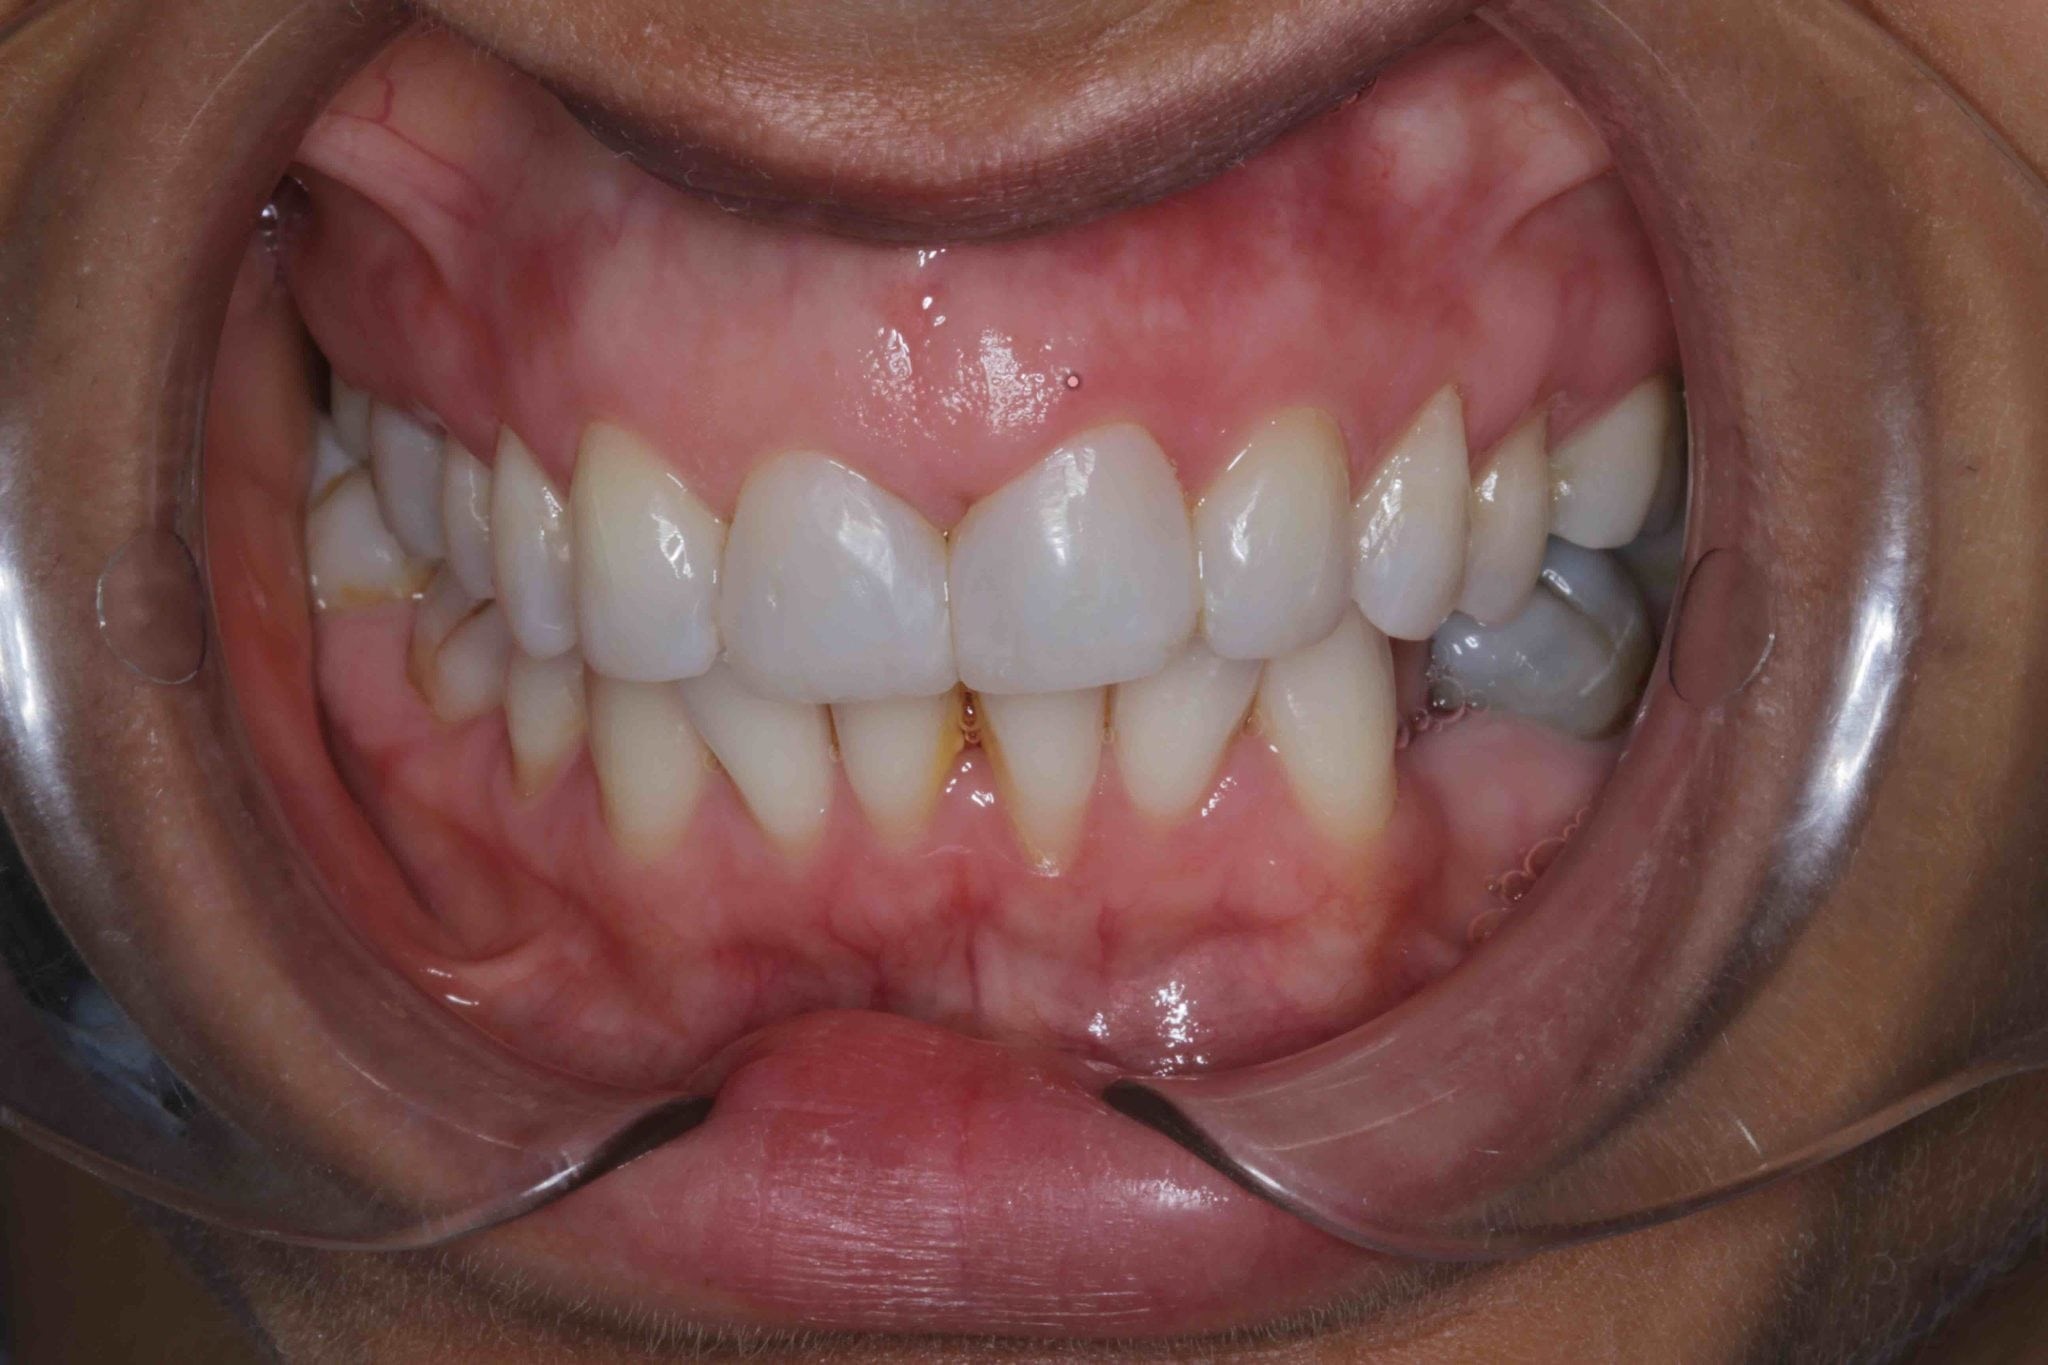

عکس کامپوزیت دندان، تصویری از دندانهای بیمار است که قبل و بعد از انجام عمل کامپوزیت تهیه میشود. این عکسها برای ارزیابی وضعیت دندانها، رنگ آنها و میزان ناهمواری سطح دندانها به کار میروند.

در عکس قبل از کامپوزیت، میتوان نواقص دندانها مانند شکستگی، ترک خوردگی، تغییر رنگ، فواصل بین دندانی و نامرتبی دندانها را مشاهده کرد. در عکس بعد از کامپوزیت، این نواقص برطرف شدهاند و دندانها ظاهری سالم، یکدست و زیبا پیدا کردهاند.

عکسهای کامپوزیت به دندانپزشک کمک میکنند تا روند درمان را به درستی برنامهریزی کند، رنگ مناسب کامپوزیت را انتخاب کند و پیشرفت کار را در طول درمان رصد نماید. همچنین این عکسها میتوانند برای بیمار نیز مفید باشند، زیرا به او نشان میدهند که دندانهایش بعد از کامپوزیت چه ظاهری خواهند داشت.

در عکس اول و قبل از کامپوزیت دندان مشخص است که فاصله زیادی بین دو دندان جلو وجود دارد. همچنین دندانهای پایین کج و نامرتب هستند. بنابراین از کامپوزیت دندان برای بستن فاصله دو دندان بالایی قسمت جلویی فک و منظم کردن ۶ دندان پایین در قسمت جلویی فک استفاده شده است. در عکس بعد از کامپوزیت دندان مشخص است که رنگ بندی کامپوزیت کاملا همرنگ دندان های طبیعی بیمار انتخاب شده است.